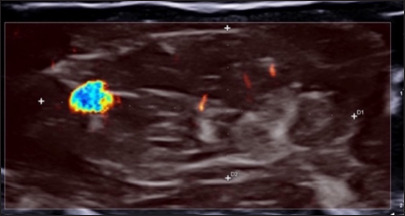

背景:动静脉畸形血管瘤(AVMH)是一种罕见的良性血管病变,常位于头部和颈部,很少发生在四肢。早期症状通常是非特异性的,这使得与其他良性病变(如神经鞘瘤)的临床鉴别诊断尤其具有挑战性。病例描述:我们报告一例25岁男性前臂病变。最初,临床和影像学特征提示神经鞘瘤,因为它位于周围神经,没有明显的血管征象。病变通过手术切除。组织病理学检查显示与AVMH相符的特征,证实了诊断。结论:该病例强调了包括AVMH在内的软组织病变鉴别诊断的重要性,特别是当位于周围神经的过程中,并模仿其他良性肿瘤,如神经鞘瘤。

Background: Arteriovenous malformation hemangioma (AVMH) is a rare, benign vascular lesion, often located in the head and neck and less frequently in the limbs. Early symptoms are typically nonspecific, making the clinical differential diagnosis with other benign lesions, such as schwannomas, particularly challenging.

Case description: We report the case of a 25-year-old male presenting with a lesion in the forearm. Initially, the clinical and imaging features suggested a schwannoma, due to its location along a peripheral nerve and the absence of distinctive vascular signs. The lesion was surgically excised. Histopathological examination revealed features consistent with AVMH, confirming the diagnosis.